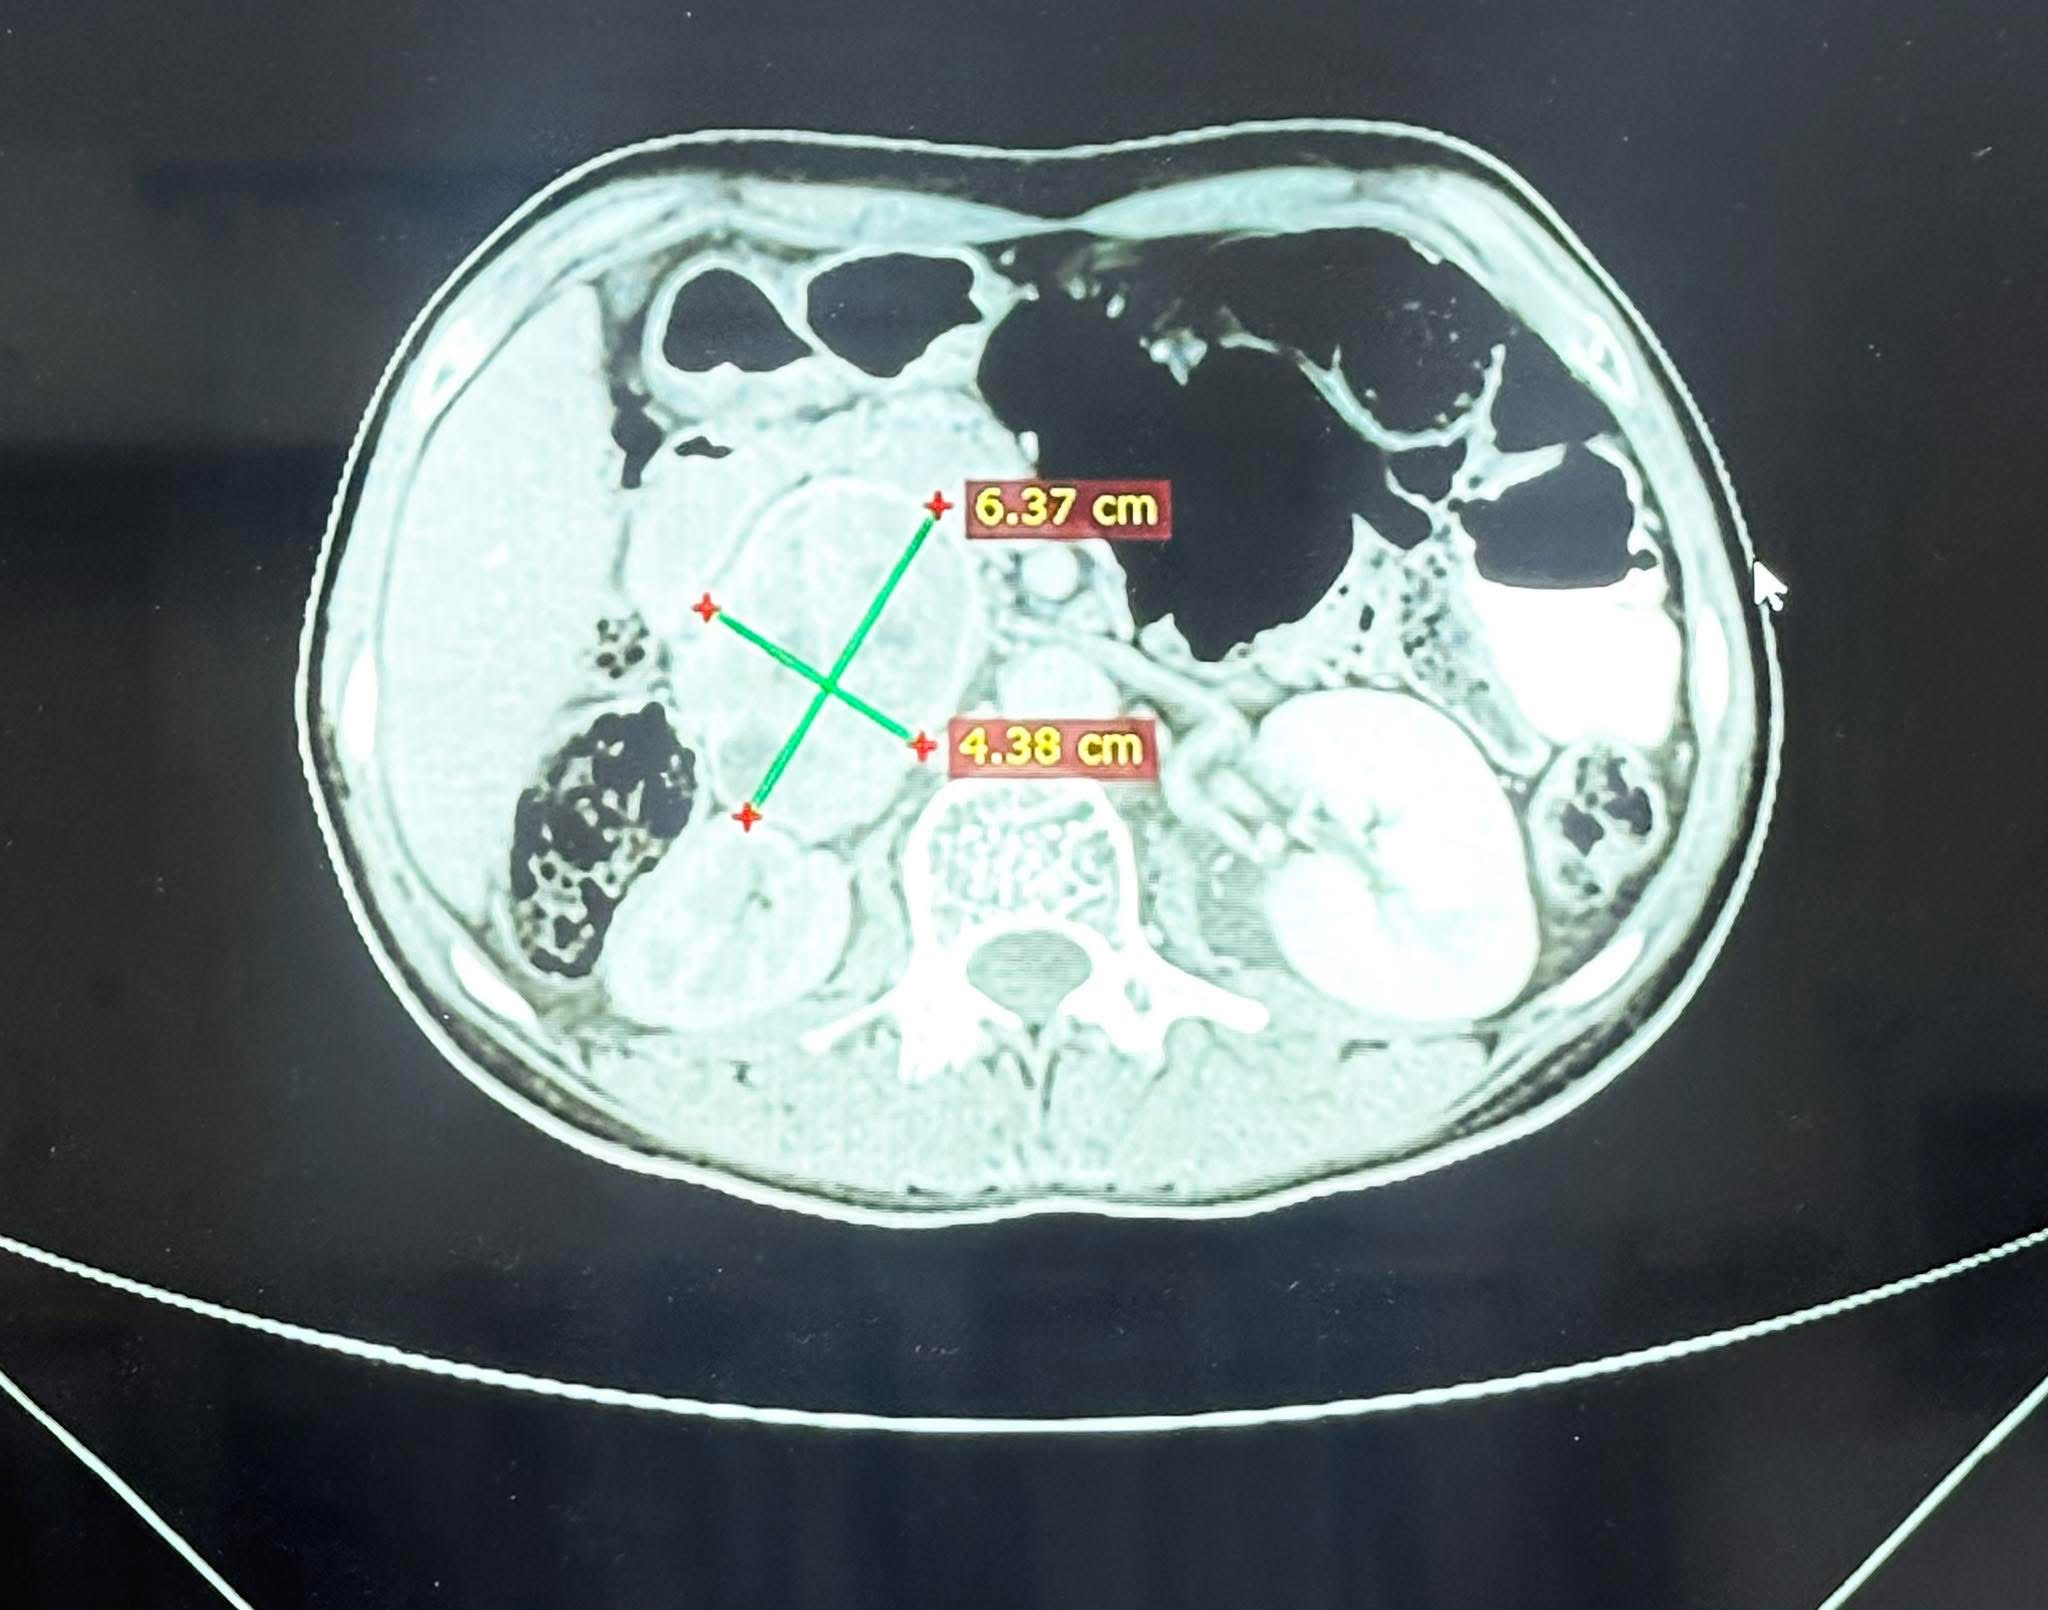

المريض، البالغ من العمر ٢٥ عامًا ومن سكنة محافظة نينوى / الموصل، أُحيل إلى مركز الفيحاء التخصصي بعد معاناة طويلة من ارتفاع شديد في ضغط الدم وتسارع حاد في ضربات القلب. وبعد إجراء الفحوصات اللازمة، تبيّن وجود ورم كبير في الغدة الكظرية اليمنى، يفرز كميات مرتفعة جدًا من هرمون الأدرينالين (Pheochromocytoma)، ما شكّل خطرًا كبيرًا على حياته. كما أظهرت الفحوصات أن الورم كان مخترقًا من الأوعية الدموية الرئيسية، مما زاد من تعقيد وخطورة التداخل الجراحي.

ويُعد هذا الورم أكبر ورم كظري يفرز هورمون الادرينالين تم التعامل معه من حيث الحجم.